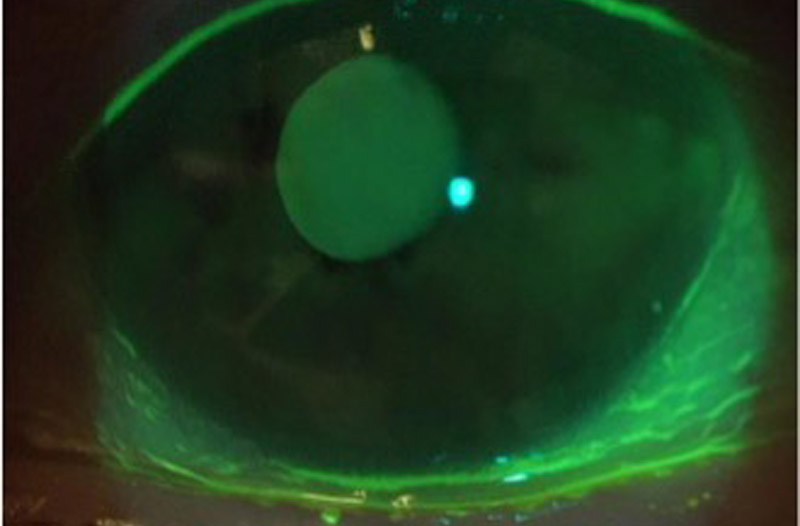

涙の量は改善しました。

目頭にチューブが入っています。